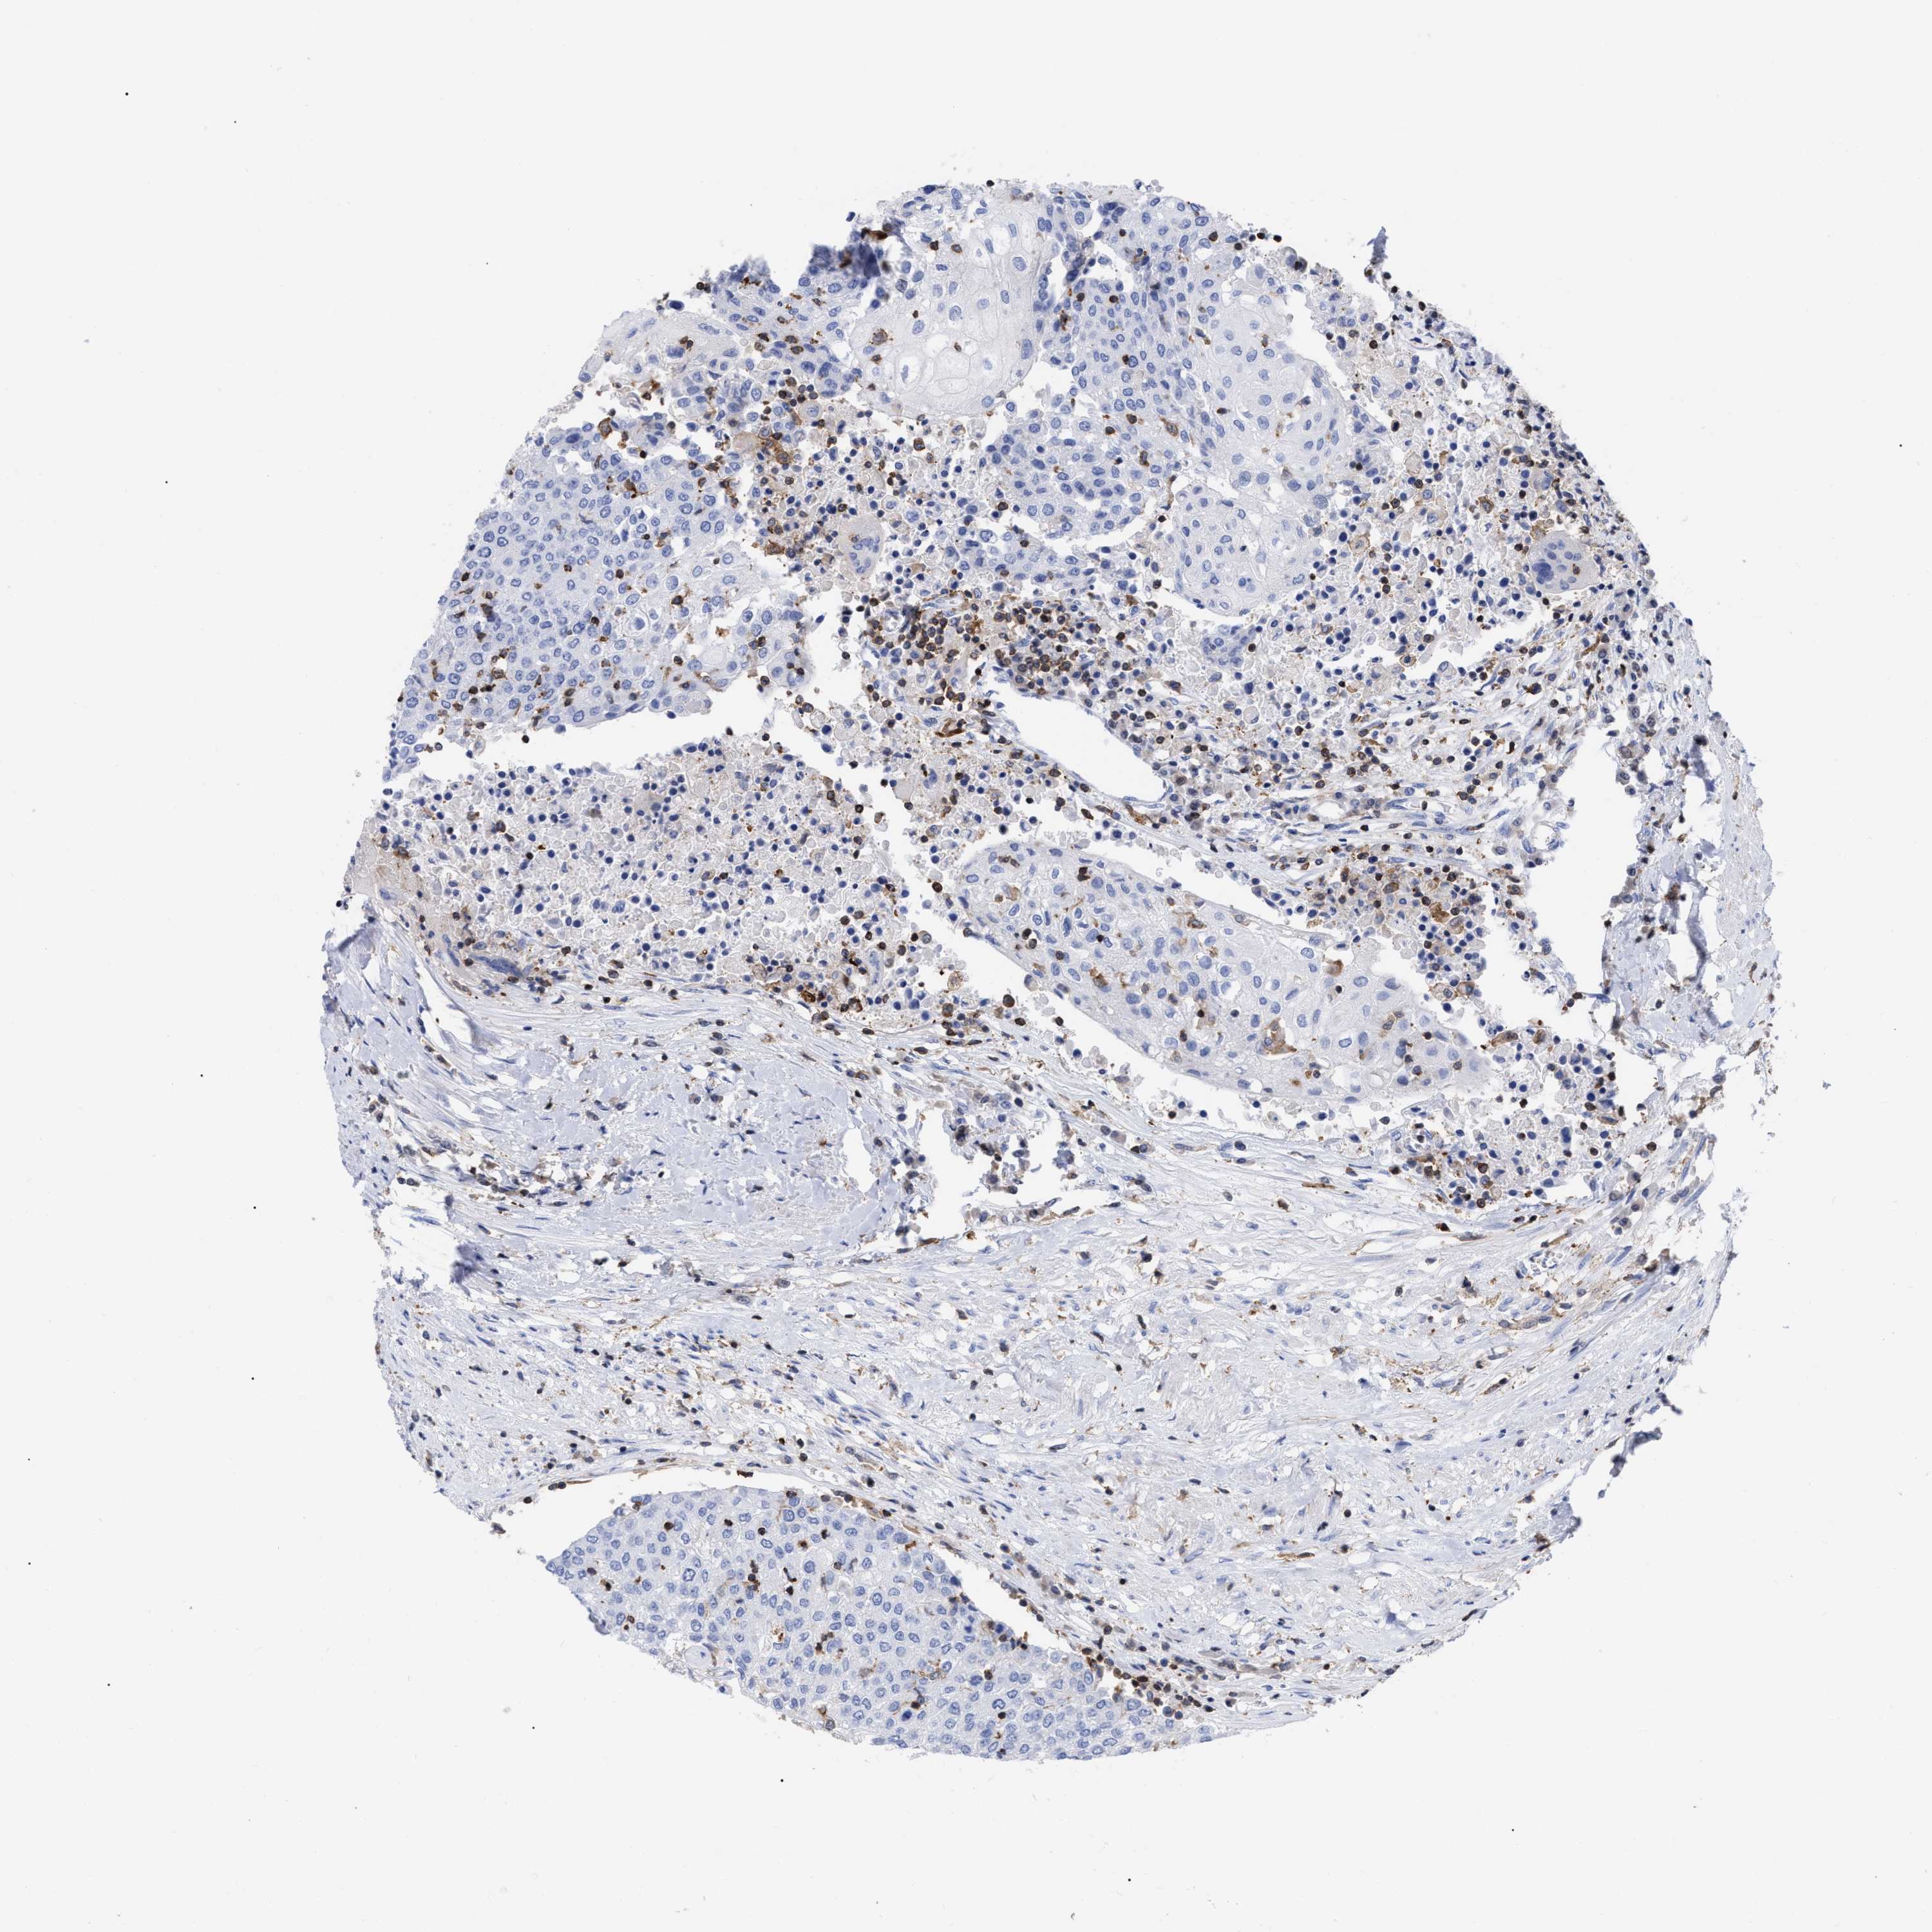

UROTHELIAL CANCER - Protein expressioni

A mouse-over function shows sample information and annotation data. Click on an image to view it in a full screen mode. Samples can be filtered based on level of antibody staining by selecting one or several of the following categories: high, medium, low and not detected. The assay and annotation is described here.

Antibody stainingi

Antibody staining in the annotated cell types in the current human tissue is reported as not detected, low, medium, or high, based on conventional immunohistochemistry profiling in selected tissues. This score is based on the combination of the staining intensity and fraction of stained cells.

Each image is clickable and will lead to virtual microscopy that enables deeper exploration of all samples and also displays staining intensity scores, fraction scores and subcellular localization as well as patient and tissue information for each sample.

Antibody HPA019143

Staining

High

Medium

Low

Not detected

Intensity

Strong

Moderate

Weak

Negative

Quantity

>75%

75%-25%

<25%

None

Location

Nuclear

Cytoplasmic/membranous

Cytoplasmic/membranous,nuclear

Urothelial carcinoma, Low grade

Urothelial carcinoma, High grade